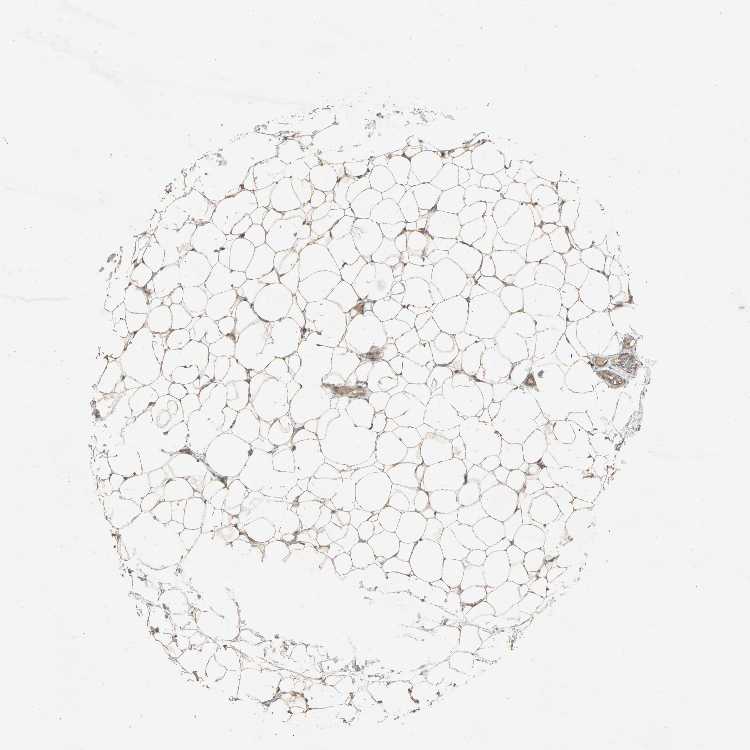

SOFT TISSUE 1 - Antibody stainingi

Antibody staining in the annotated cell types in the current human tissue is reported as not detected, low, medium, or high, based on conventional immunohistochemistry profiling in selected tissues. This score is based on the combination of the staining intensity and fraction of stained cells.

Each image is clickable and will lead to virtual microscopy that enables deeper exploration of all samples and also displays staining intensity scores, fraction scores and subcellular localization as well as patient and tissue information for each sample.

Antibody HPA005651

Peripheral nerve Medium

SOFT TISSUE 2 - Antibody stainingi

Fibroblasts Medium